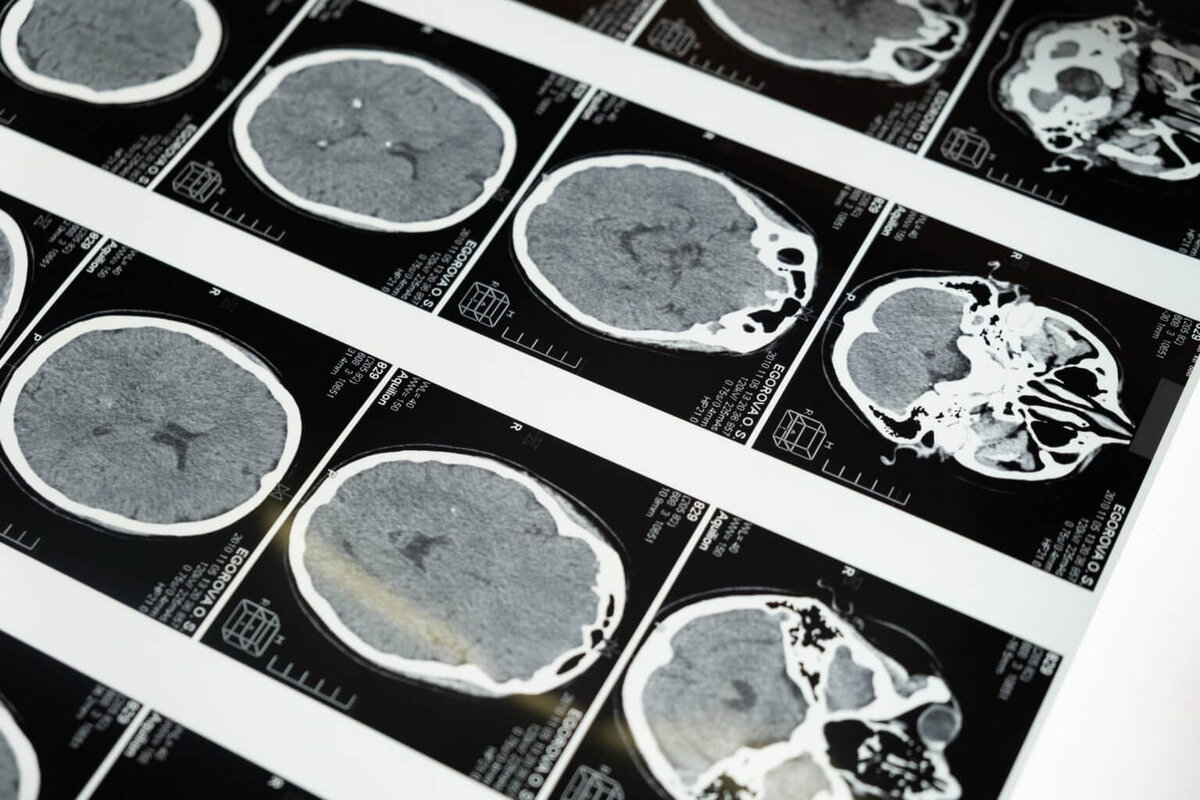

Ученые исследовали мозг молодых и пожилых людей, столкнувшихся с психологическими страданиями других граждан. Участникам были показаны короткие видеоролики о людях, переживающих эмоциональный стресс в разгар стихийных бедствий. Для сравнения добровольцам также показали видео нейтрального эмоционального содержания. Активность мозга специалисты оценивали с помощью МРТ.

Это особенно заметно на сети мозга, которая активируется в состоянии покоя. Активность часто нарушается из-за депрессии или тревоги. У пожилых граждан задняя поясная кора, которая обрабатывает автобиографическую память, показывает увеличение связей с миндалевидным телом, обрабатывающим важные эмоциональные стимулы. Такие связи сильнее у людей с высокими показателями тревожности или негативными мыслями.